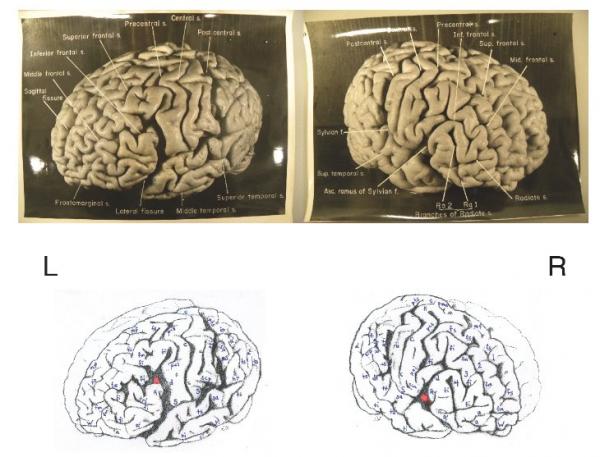

بالصور دماغ ألبرت آينشتاين مختلفه عن كثير من الناس نوبانجى